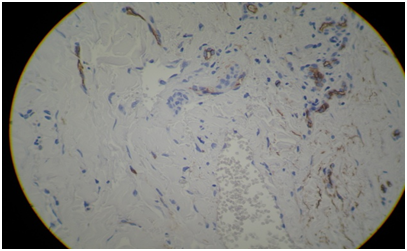

A female patient of 51 years of age consulted in March 2018 for asymptomatic, recurrent and autoinvolutive erythematous papules of 4mm in the left breast of 3months of evolution (Figures 1-3). Each lesion lasted a week. The patient was in oncological follow-up for left breast cancer of invasive ductal type diagnosed in 2016. She underwent quadrantectomy, axillary emptying and adjuvant chemotherapy with 4cycles of atracyclines (cyclophosphamide 1000mg and doxorubucine 100mg) and 12weeks of paclitaxel 80mg/m2/week. Additionally, they performed three-dimensional radiotherapy (RT) from July to October 2016. Then she continued on tamoxifen orally until today. With presumptive diagnoses of atypical vascular proliferation versus angiosarcoma versus cutaneous metastases, a punch biopsy was done of the most infiltrated lesion. The histology showed the presence in the reticular dermis of some irregular vascular channels that dissected the collagen, upholstered by flat endothelial cells or cuboids, without evidence of significant cytological atypia or mitosis. Focal erythrocyte extravasation coexisted (Figure 4). In the immunohisto chemistry, she had CD34 negative in the endothelium of the vascular channels, CK AE1 and AE3 and CK 7 negative for neoplastic cells and CD 68 positive in macrophage isolates (Figure 5). These changes were compatible with an atypical vascular lesion .

Figure 5 Immunohistochemistry CD68 positive for macrophages.